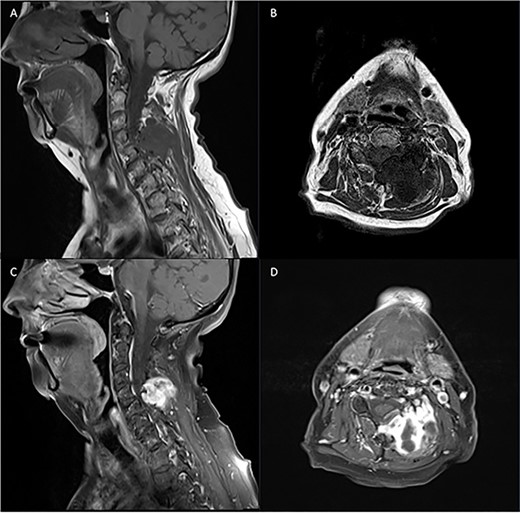

Pre-operative spinal imaging showed a well-circumscribed, cystic parasagittal spinal mass eroding through the lamina and pushing the thecal sac and largely indicative of a paraspinal myxoma (Fig. 1). The patient underwent a biopsy in the first instance to guide diagnosis and subsequently proceeded to resection of the tumour.

Pre-operative T1 and T2 weighted MRI: left-sided extra-axial mass at C4/5 hypointense on T1 and hyperintense on T2.